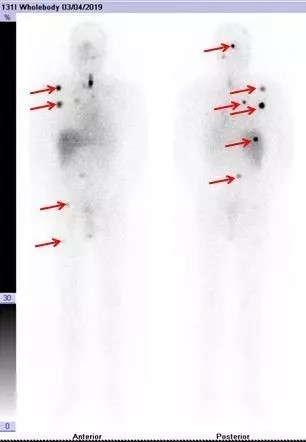

经过 MDT 多学科会诊后建议患者停用优甲乐,同时低碘饮食 1 月后行碘-131 治疗。1 月后复查甲状腺球蛋白(Tg)334ng/ml,考虑还存在其他部位肿瘤转移病灶,给予 200mCi 大剂量碘 131 治疗。治疗后碘-131 全身 SPECT/CT 显像提示全身多发骨转移(如图 1)。

图 1:红色箭头所示颅骨、右锁骨、肋骨、右股骨等全身多发性骨转移病灶